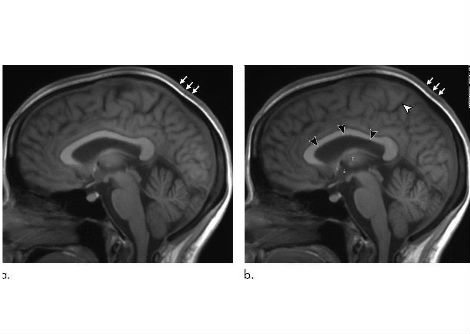

رحلات الفضاء طويلة المدى يمكن أن تغير حجم دماغ رائد الفضاء بشكل دائم